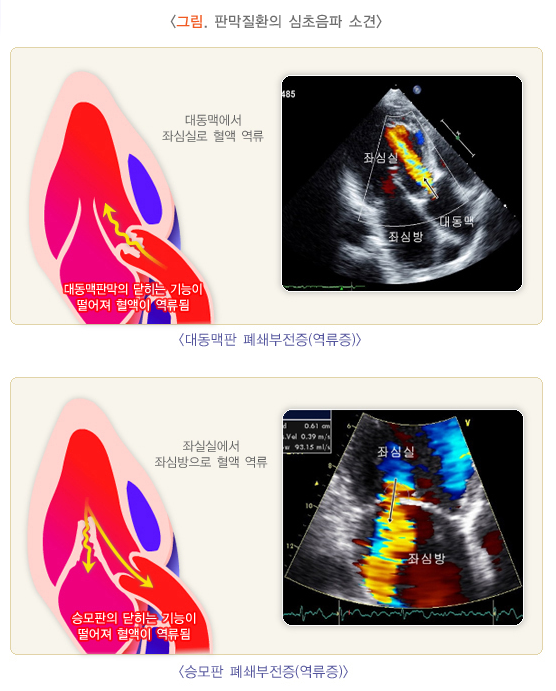

- 승모판이 파열되면 좌심실에서 좌심방으로의 혈액 흐름이 방해받습니다. 이는 혈액이 비정상적으로 역류하여 심장이 제대로 펌프질하지 못하게 만듭니다. 이로 인해 좌심실에 과도한 압력이 발생하며, 혈액 순환에 문제가 생깁니다.

- 혈액 역류는 결국 호흡 곤란, 심부전, 폐부종 등의 심각한 증상을 유발할 수 있습니다.

- 기본적인 심장 모니터링: **심전도 (ECG)**나 심장 초음파(Echocardiogram) 등을 통해 심장의 상태를 실시간으로 모니터링합니다. 이는 심장의 펌프 기능, 부정맥, 혈류 흐름 등을 파악하기 위해 중요합니다.

- 심장 초음파(Echocardiogram): 수술 후, 정기적인 심장 초음파 검사를 통해 승모판 기능, 심장 기능, 혈류 상태를 평가합니다. 판막 기능을 주기적으로 확인하고, 혈액 역류나 심장 크기 변화 등을 감지합니다.